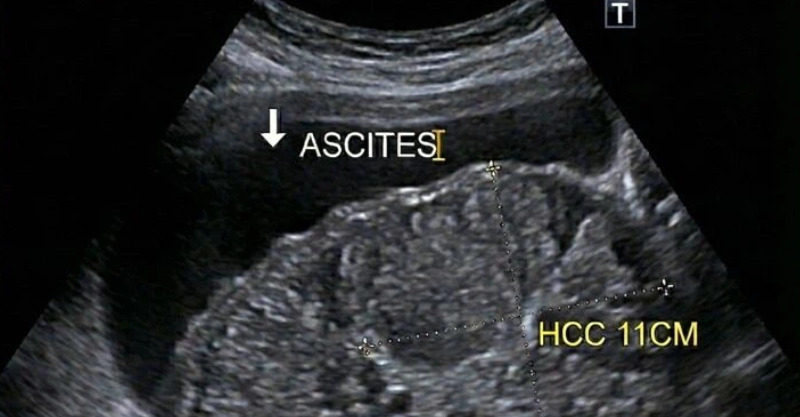

(示意圖/圖片來源:Getty Image)